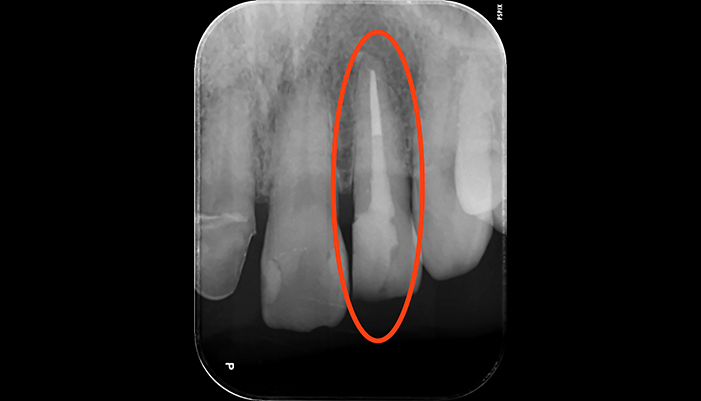

治療前

治療後

| 主訴 | 歯茎が腫れている |

|---|---|

| 治療期間 | 2回 |

| 費用 | 再根管治療154,000円(税込)+ ファイバーコア44,000円(税込)= 198,000円(税込) |

| 治療内容 | ラバーダムを用いて無菌的な環境下で根管治療を行いました。 マイクロスコープ下で虫歯を完全に取り切り、NiTiファイルを用いた根管形成、薬液や超音波器具による洗浄、その後根管内をさらに消毒するため水酸化カルシウムを入れて仮の蓋をしました。 2回目は体に馴染みの良い材質による充填、被せ物を支え、再感染しないように土台を立てました。 |